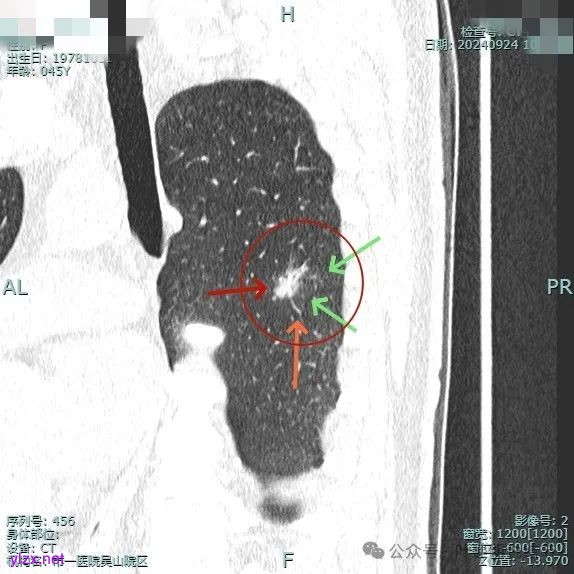

我们先来看2024年9月时的影像:

病灶1:

右下背段混合密度病灶,边上不太清爽,有片状淡磨玻璃影,实性部分密度较高。

感觉病灶有点晕征似的,表面不平,灶内不太致密。

有小血管进入,似有晕征。

离胸膜近但牵拉不明显,病灶边缘有细毛刺,较短且不太锐利。

边缘少许磨玻璃成分,血管进入明显。

瘤肺边界稍显不清。